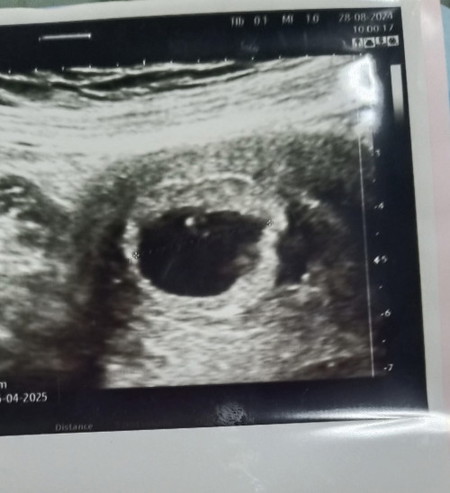

ซาวด์อายุครรภ์7วีค หมอแจ้งว่าพบถุงตั้งครรภ์ แต่ไม่เห็นตัวอ่อน นัดอีกที่ตอน9วีค แบบนี้มีโอกาสเจอน้องไหมคะ😔